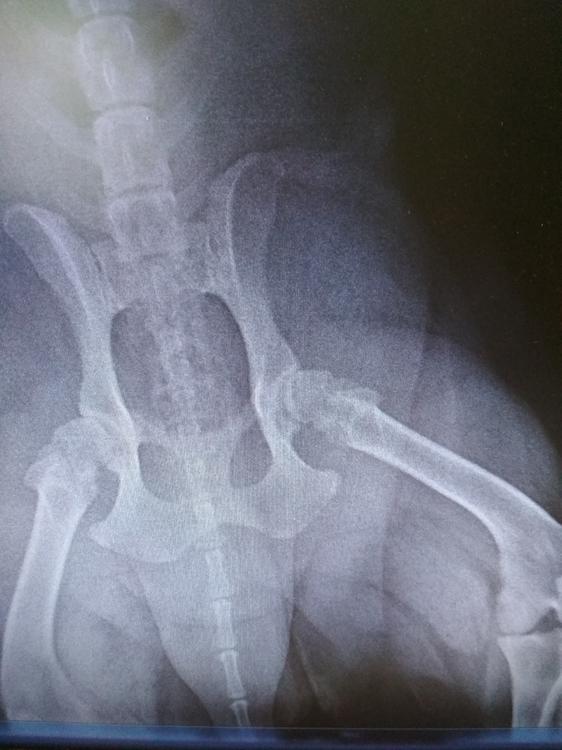

Kerta Опубликовано 9 марта, 2020 Опубликовано 9 марта, 2020 будет много буков, короче не получается... Лабрадор ретривер, сука, 20.03.2012 г.р.,кастрация 25.08.19г. на тот момент вес 34,5. С лета 19 года начала постепенно снижаться активность (не всегда приходит на кухню, когда готовлю, реже встречает у дверей). Стала плохо переносить жару—сильная одышка, после прогулки в спокойном состоянии больше часа пыхтит. В конце января 2020 г. перестала самостоятельно запрыгивать в машину, пропоили превикокс 227 в течение 5 дней, без эффекта. вес 37,5. Питание овощи притушенные +сырая говядина (калтыки, обрезь). В начале февраля начала садиться на прогулке, одышка не постоянно. на прогулке обратили внимание, что при нагрузках сереет язык. Консультация кардиолога (эхо сердца, экг, рентген грудной клетки)—все в пределах возрастной нормы. На рентгене грудной клетки значительное сужение трахеи в шейном отделе, рекомендована шлейка и при ухудшении дальнейшее обследование. По лестнице поднимается тяжеловато. Дома старается лежать, на диван запрыгивает самостоятельно с разбега, при попытке запрыгнуть с места задние лапы срываются, после этого кратковременная скованность походки. Хромоты нет, нарушения координации нет. Просто бежит резвой рысью и садится, от 15-30 сек до 2-3 минут сидит ровно, спокойно, смотрит по сторонам, нюхает воздух, может лечь, сама легко встает и бежит дальше, прогулки до полутора часов по лесу, во время прогулки активна, лазит по сугробам, играет с собаками. никакой периодичности присаживаний нет. Когда беру на поводок и идем домой, садится чаще, может через каждые 10-15 метров. Результаты узи—гепатит?, холецистит. Свободной жидкости в брюшной полости нет. Лечение—урсосан, гептрал, амоксиклав. ОАК, биохимия—повышены печеночные показатели незначительно. В начале марта. Вес 37. При неврологическом обследовании рефлексы не снижены, суставы подвижны, безболезненны, кроме тазобедренного слева (по рентгеновскому снимку—артроз, остальное норма). снимок без седации (ну вот такая ветеринария...). Рентген позвоночника пока не описали, со слов все неплохо. После обследования в течение 2 суток скованность походки, перемежающаяся хромота (связываю с тем, что при осмотре ей гнули лапы, вытягивали для снимка, снимок был без наркоза), дала таблетку НПВС, состояние улучшилось незначительно. и тут кто то видит артроз, кто то с ходу дисплазию обеих суставов, кто то говорит, что либо был перелом шейки бедренной кости либо скоро сломается снимки только такие: